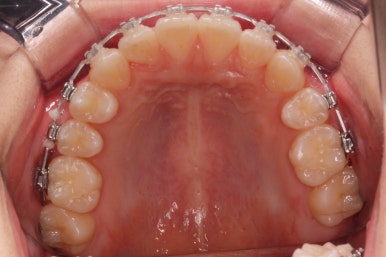

부산교정 키다리아저씨치과에서 결손치아 부분을 임플란트 하지 않고 치아교정을 통해서 개선한 이번 환자분의 치료를 마무리한 사진입니다.

치열은 가지런해졌고, 틈새는 없이 마무리되었습니다. 아랫니가 3개이지만 마치 4개인 것처럼 마무리하였고, 따라서 위~아래 치열의 중앙도 거의 맞게 마무리하였습니다.

(한 쪽은 송곳니를 앞니 대신 사용해야 했어서 크기 문제로 완벽히는 중앙을 맞추기 힘듭니다.)